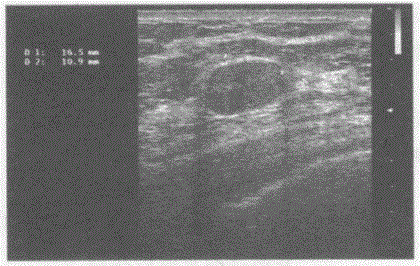

问题 临床资料:男,50岁,自述胃癌术后3年余。 超声综合描述:右锁骨上窝扫查可见数个长圆形低回声区,最大1.7cm×1.1cm,边界尚清,内回声欠均匀,部分互相融合,CDFI:内可见少许动脉血流信号。见下图及彩图。 {图1} 超声提示:

选项 A.右锁骨上窝淋巴结结核 B.右锁骨上窝囊肿 C.右锁骨上窝肿大淋巴结(淋巴结转移瘤) D.右锁骨上窝正常淋巴结声像图

答案 C